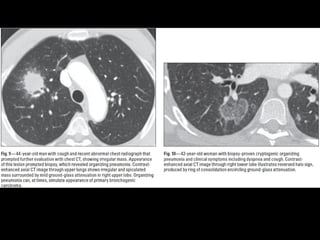

COP

• Ex BOOP

• Asociada a : colágeno, infecciones, EII,

radiación, toxicidad, transplante órganos

Criptogénica: idiopática

55 h=m

4- 6 semanas con síntomas de gripe

Buen pronóstico

COP CT

• Consolidaciones parcheadas

• Broncograma aéreo Signo halo inverso

• Vidrio esmerilado periférico o peribroncovascular

• Crazy paving

• LI

• Nódulos, cavitarse

• Puede simular neumonía

• Reticulación subpleural

• Derrame pleural

Bilateral or unilateral patchy alveolar airspace consolidation is revealed,

often subpleural and peribronchial in location and mainly in the lower

zones.

Generally, the infiltrates gradually enlarge from their original size or

new infiltrates appear.

Consolidation is often nonsegmental and varies from 2 to 6 cm in

diameter.

Cavitary BOOP that mimics tuberculosis and cavitating opacity after

lung transplantation has been reported.

An air bronchogram may be present.

Nodules 3-5 mm in diameter are seen in approximately one half of

patients; nodules may be migratory.

Basal linear opacities are linked to a poorer prognosis.

Unilateral focal or lobar consolidation occurs in 5-31% of patients.

Miliary pattern is rare.

Pleural thickening occurs but pleural effusions are rare.